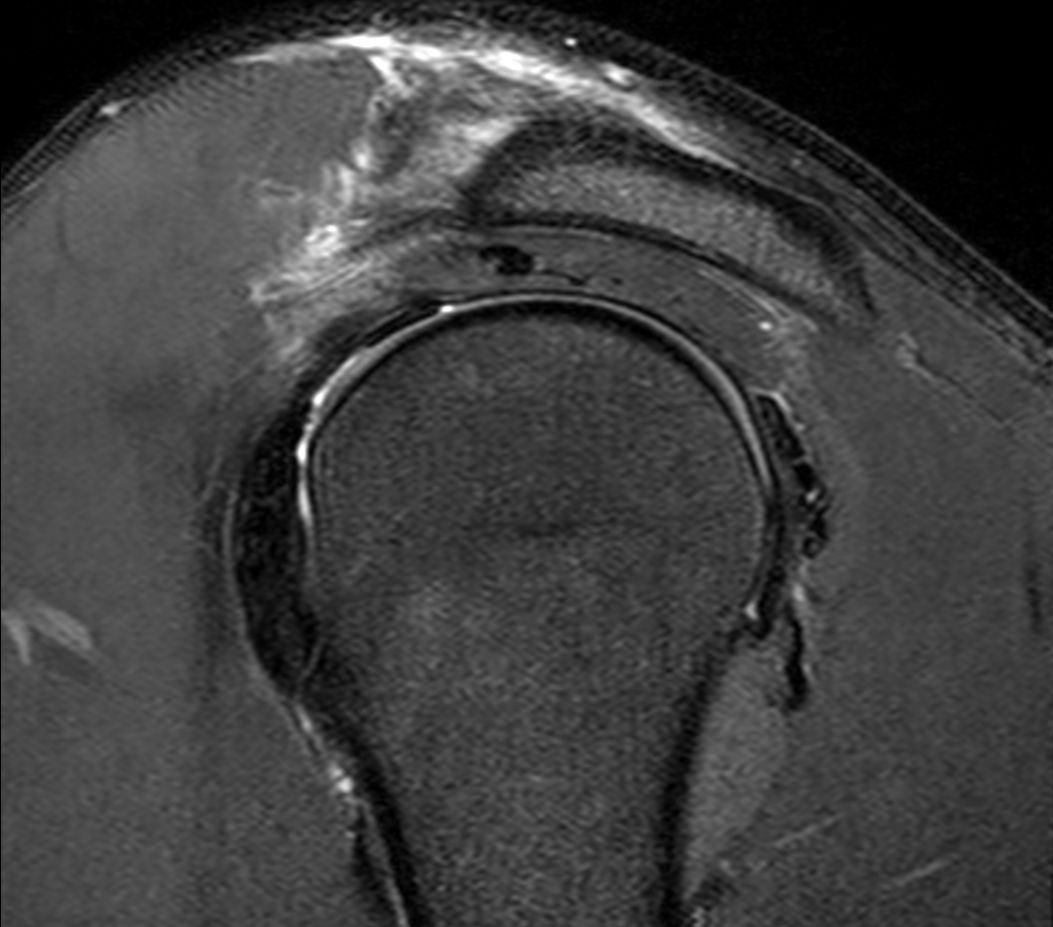

Sagittal T2w SPAIR